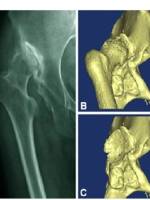

C型先髋患者(俗称高脱位先髋),股骨头完全在髋臼外,若产生假髋臼,我们叫C1型,没有假髋臼叫C2,C1和C2的分类除了可以从是否有假髋臼来看,从股骨侧也有明显的差异。

下图可见假髋臼和髂骨骨赘